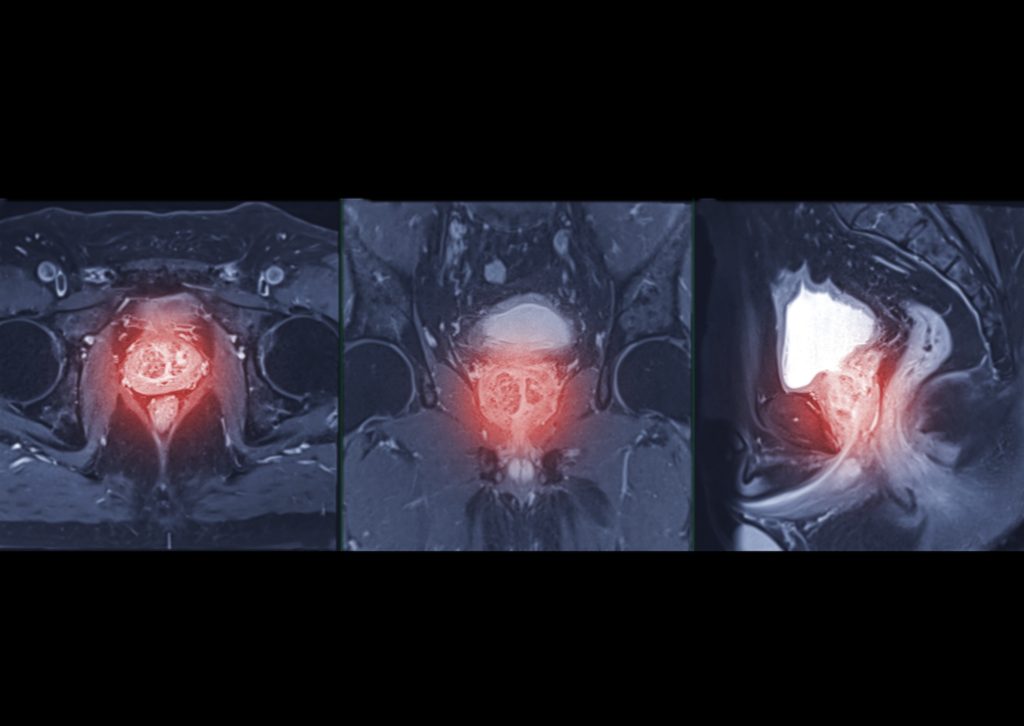

Prostata

Generellt sett har män inte lika många krämpor och besvär som kvinnor – kanske är det därför som vi kvinnor kallats för ”det svagare könet”! Ett av de besvär som män många gånger drabbas av med åren är en förstorad blåshalskörtel, eller prostata, som det oftast kallas. Prostatan kan ses som en mötesplats, då både […]